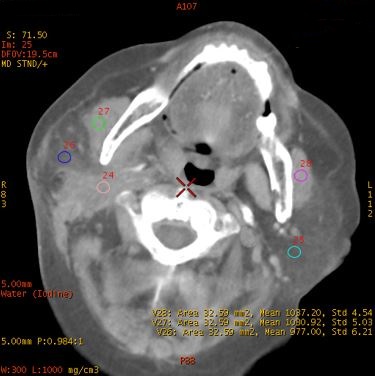

碘基图

直方图

碘基-直方图:直观显示了不同ROI面积下碘含量的差异。